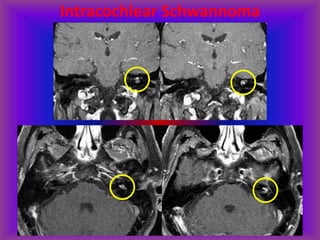

Intracochlear Schwannoma